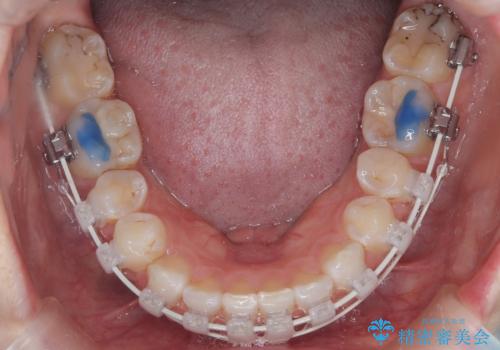

- 右上の八重歯と歯のデコボコ、そして上下の歯の中心(正中)のズレを気にされて来院されました。精密な検査の結果、歯が並ぶスペースが不足しているため、上顎の小臼歯(前から数えて4番目の歯)を抜歯し、そのスペースを利用して歯並び全体を整える治療計画を立案しました。これにより、八重歯の位置を適切に改善し、叢生(歯のデコボコ)を解消するとともに、上下の正中線のズレも改善することを目指します。

今回の矯正治療では、歯が並ぶスペースを確保するため、上顎の小臼歯を抜歯しました。抜歯によってできたスペースを有効活用し、ワイヤーやブラケットを使って右上の八重歯を適切な位置へ移動させ、叢生を解消していきました。また、治療を通じて上下の歯の中心である正中線のズレも改善するよう、慎重に歯を動かしました。治療の結果、長年気にされていた八重歯と歯のデコボコが解消され、上下の正中線も一致。機能的にも審美的にもバランスの取れた、美しい歯並びと笑顔を獲得していただけました。